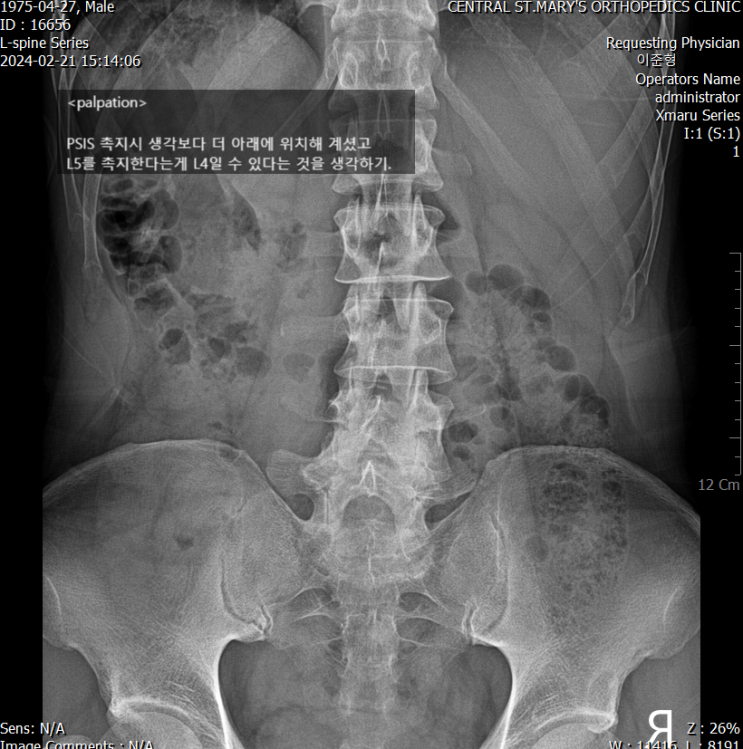

x-rayㅣ 퇴행성 요추 + 변형

촉진점이 특이. PSIS가 생각보다 훨씬 아래에 있으셨고 L5 생각 없이 촉지하면 꼭 천골처럼 느껴질 수...